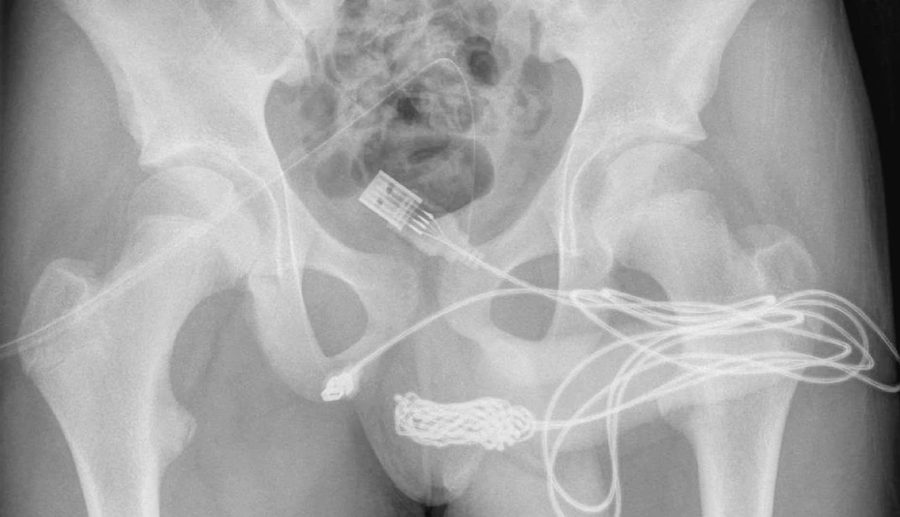

यो घटना कहिले भएको हो थाहा छैन, तर यो अनौठो घटना नोभेम्बर २०२१ मा युरोलोजी केस रिपोर्टमा रेकर्ड गरिएको थियो। डाक्टरहरूले साइन्स डाइरेक्ट रिपोर्टमा लेखेअनुसार यूएसबी केबलको दुईवटा डिस्टल पोर्टहरू बाहिरी मूत्रमार्ग मेटसबाट बाहिर निस्किएको पाइएको थियो, जबकि तारको बीच भाग मूत्रमार्ग भित्रै फसेको थियो।

उनीहरूको रिपोर्टमा, डाक्टरहरूले बिरामी मानसिक स्वास्थ्य विकारको इतिहास नभएको एक फिट र स्वस्थ केटा थियो भन्ने उल्लेख छ। केबुलभित्र गाँठो बनेकाले पिसाबमार्गमा अड्किएको केबुललाई धातुको रडको सहायताले हटाउन डाक्टरले सकेनन्। यस्तो अवस्थामा उनले ति किशोरको शल्यक्रिया गर्नुपर्यो।

सर्जिकल टोलीले केटाको गुप्तांग र गुदद्वारको बीचमा चीरा बनायो, जसले गर्दा उसको भित्र फसेको केबुलहरूमा पहुँच गर्न सकियोस्। शल्यक्रिया सफल भयो र तारको दुबै छेउलाई बाहिरी मूत्रमार्गबाट सफलतापूर्वक बाहिर निकालियो।